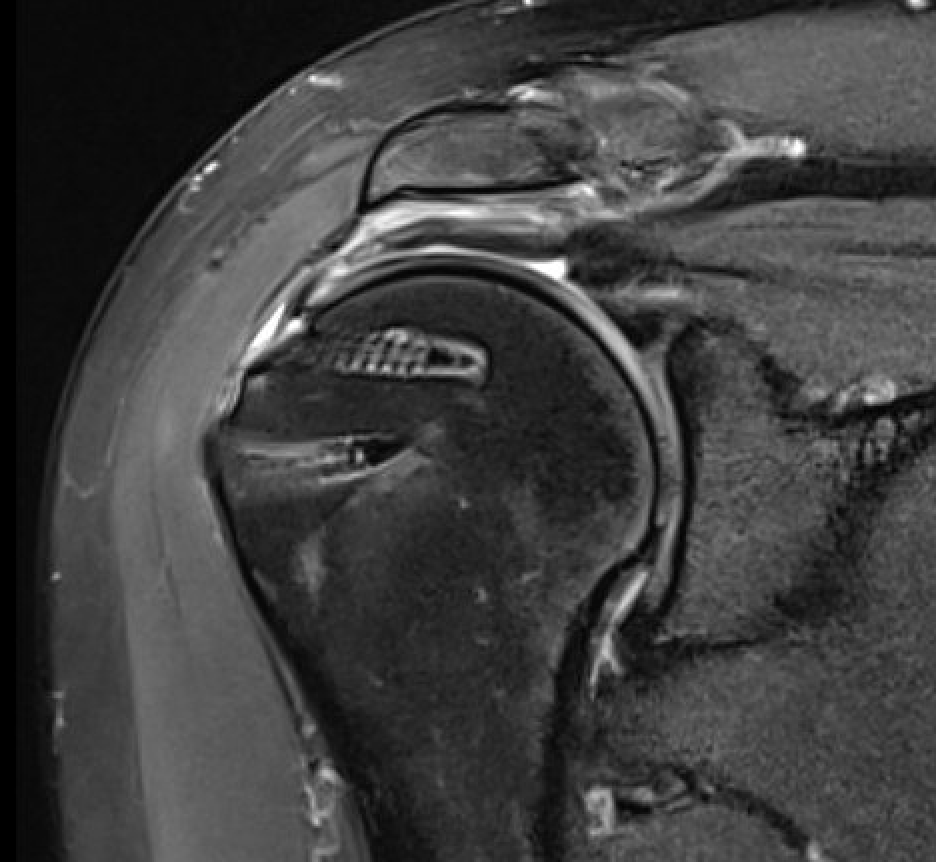

Full thickness tears

Supraspinatous Tear Minimal RetractionSS tear arthroscopyArthroscopic Suture Bridge Cuff Repair